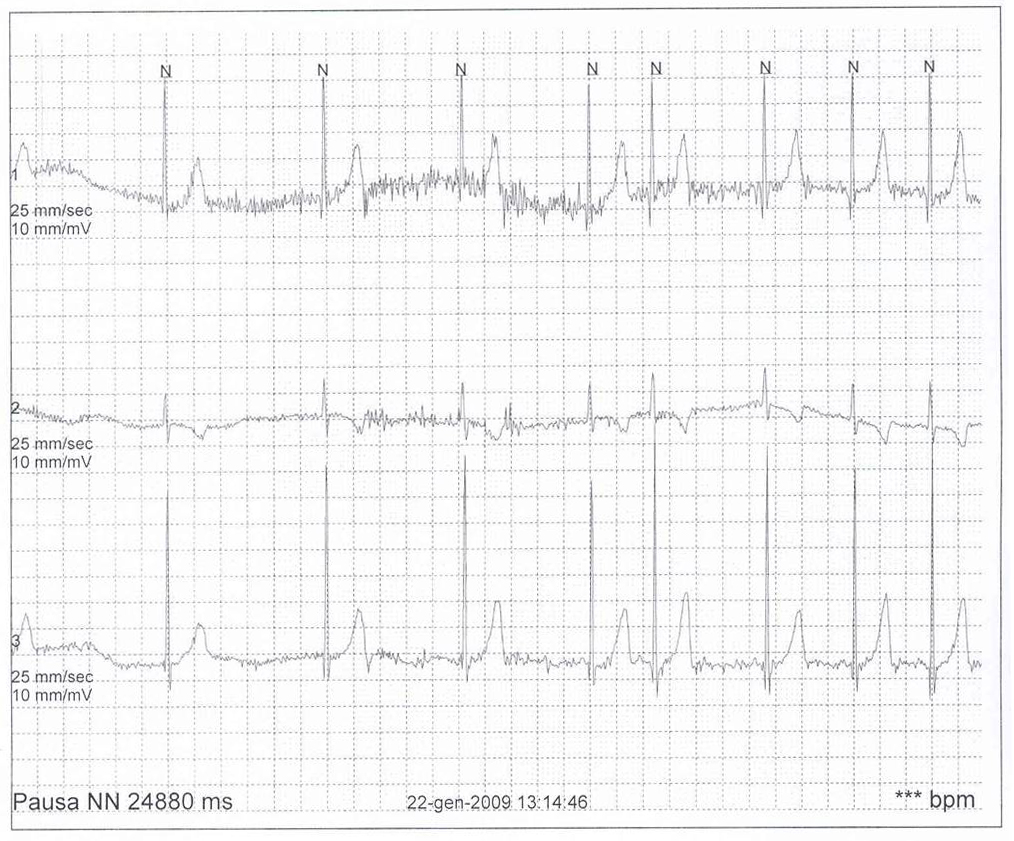

Tale ipotesi � stata poi confermata da un nuovo ECG Holter 24 ore che ha evidenziato, durante uno spasmo affettivo pallido spontaneo esitato in sincope e crisi convulsiva generalizzata, un�asistolia di circa 25 secondi (Figura 1). � stata quindi iniziata terapia vagolitica con atropina solfato per os (0,01 mg/kg/dose per 2 somministrazioni/die) per contrastare l�iperreattivit� parasimpatica ritenuta responsabile dell�asistolia. Questa terapia si � rivelata inefficace. La bambina ha infatto presentato alcune recidive di spasmo respiratorio pallido, sincope e crisi convulsiva. Vista la sua particolarit�, il caso � stato discusso su un forum di cardiologia pediatrica accessibile in rete (Pediheartnet) da cui sono emersi sostanzialmente due progetti terapeutici: il primo, di maggioranza, raggruppava i fautori dell�impianto di un pacemaker ventricolare; il secondo, di minoranza, raggruppava i fautori di una terapia farmacologica con diversi farmaci come teofillina, clonidina, sertralina, cerotto di scopolamina, glicopirrolato. Anche alla luce di tali pareri, viste le possibili complicanze relative all�impianto di un pacemaker in un bambino di 10 kg di peso, abbiamo deciso di tentare nuovamente una terapia medica con farmaci anticolinergici; in particolare, tra il cerotto transdermico di scopolamina e il glicopirrolato la scelta � caduta su quest�ultimo (alla dose di 0,5 mg per 3 volte al giorno per os) in quanto meglio dosabile nel siero. Al glicopirrolato abbiamo associato teofillina a rilascio prolungato (80 mg ogni 12 ore per os). Il razionale di questo approccio combinato risiede nella possibilit� di modulare con il glicopirrolato (un anticolinergico ad azione pi� lunga di quella dell�atropina) l�inibizione cardiaca indotta dallo spasmo pallido e nel determinare con la teofillina un effetto cronotropo positivo e una stimolazione del centro del respiro. Dall�inizio del trattamento a oggi (11 mesi di follow-up) la paziente ha continuato a presentare spasmi affettivi non solo di tipo pallido, ma anche di tipo cianotico, senza per� presentare in nessuna occasione sincope o crisi convulsiva.

Figura 1. |